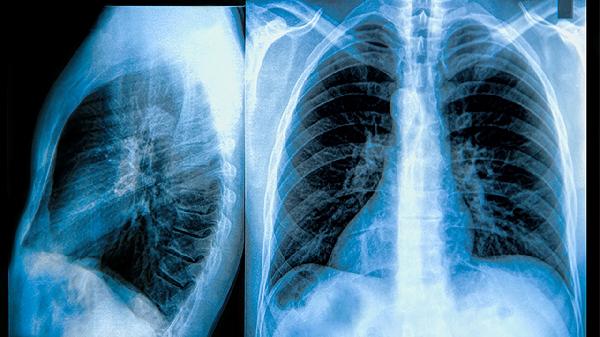

肺功能检查中,慢阻肺患者第一秒用力呼气容积与用力肺活量比值持续低于70%,支气管舒张试验阴性。哮喘患者发作期FEV1显著下降,但支气管舒张试验改善率超过12%,缓解期肺功能可恢复正常。呼出气一氧化氮检测在哮喘患者中通常明显升高。